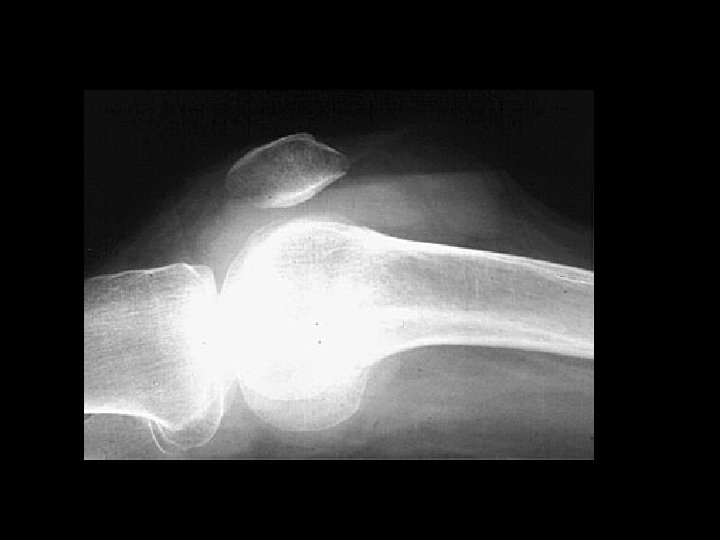

Aneurysmal bone cyst • Findings: – Lucent end of bone lesion in the proximal tibia – Slightly expansile, mild periosteal reaction – Fluid-fluid level on MRI • ddx: – Giant cell tumor – Unicameral bone cyst – Fibrous dysplasia – Chondroblastoma (rare)